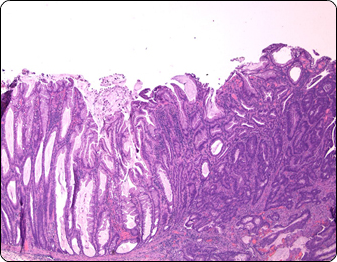

Colorectal cancer is the second most common cancer diagnosed in both men and women in the United States. Identifying the disease on time is a major challenge which demands highly specialized pathology services.

Specialized Pathology Laboratories has vast and proven experience in gastroenterology biopsies. We are proud of our undisputed professional competence, offering the highest-quality services and consultation. Our work enables better diagnosis and treatments, helping a large number of patients overcome their gastroenterology disorders.

•  Extensive experience in processing upper/lower GI and liver specimens